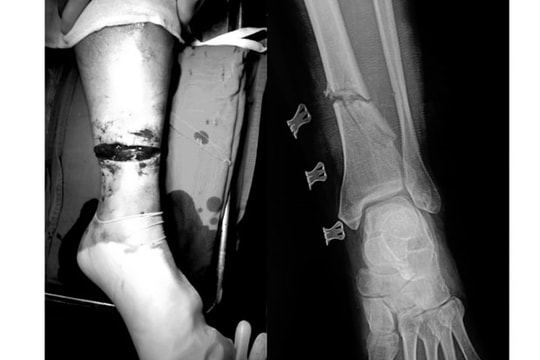

Bệnh nhân B.V.L (56 tuổi, Hòa Bình) nhập viện trong tình trạng vết thương hở đứt 3/4 chu vi cẳng chân trái, chảy nhiều máu; mất vận động cổ chân và các ngón chân, gãy hở xương chày, đứt hoàn toàn các gân cơ khu trước và sau cẳng chân, đứt bó mạch chày sau, chày trước.

Nối thành công bàn chân cho người đàn ông bị máy cắt cỏ cứa đứt lìa

Người đàn ông ở Quảng Nam nhập viện trong tình trạng choáng mất máu, tụt huyết áp do bị đứt cổ bàn chân phải vì bị lưỡi cưa của máy cắt cỏ cứa vào.